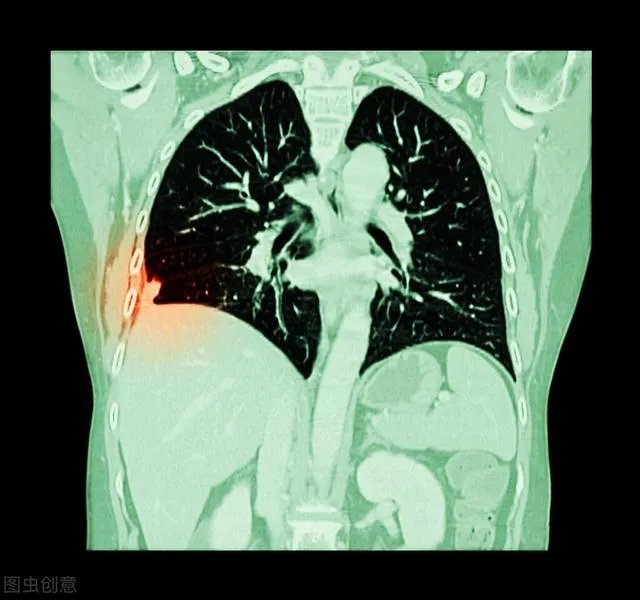

在了解肺结节之前,先给大家科普一下肺结节的定义,在医学上,我们一般将在肺部X光片或者CT检查中,直径小于3cm的高于正常肺组织的异常密度影,称之为肺结节,它的形态一般呈圆形或者类圆形,密度可以是稍高于肺组织,也可以明显高于肺组织。

根据密度的差异,肺结节又可以分为三大类型:磨玻璃结节、亚实性结节和实性结节。

根据大小的差异,又可以分小结节、微小结节等;小结节的直径一般小于10mm,在4—10mm之间,而微小结节的直径一般就是小于4mm的。